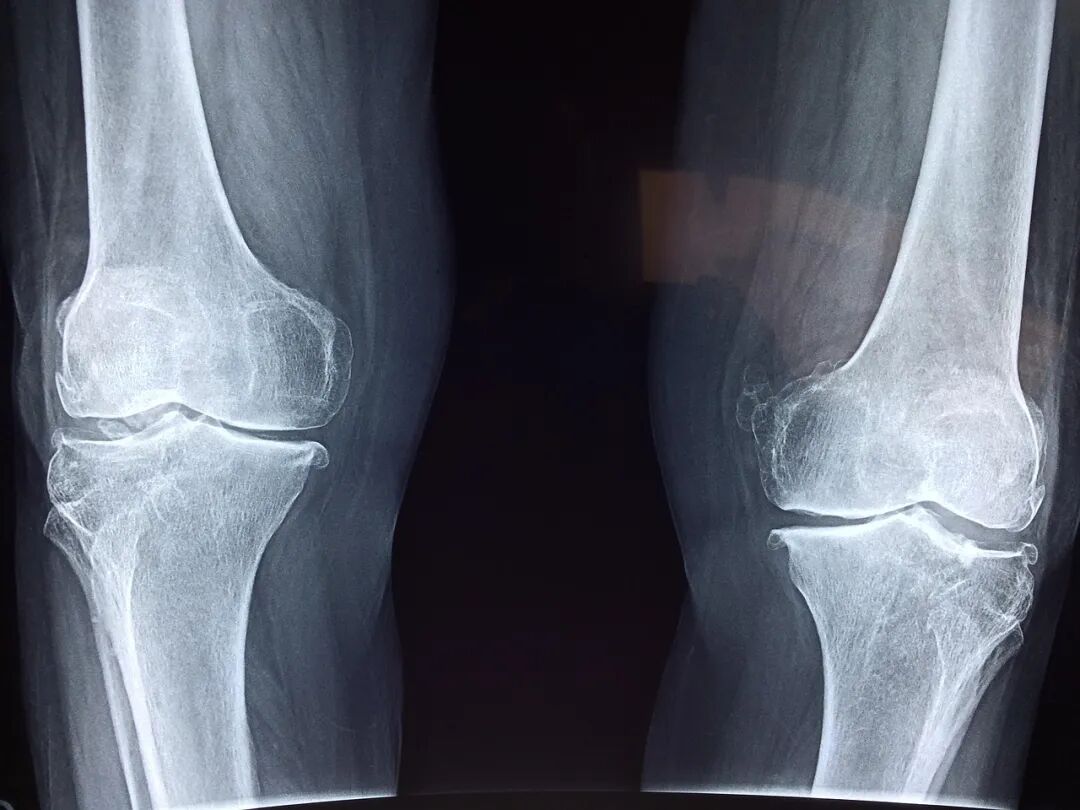

2018年2月,雷某(化名)入职白云区某物流公司担任装卸工,双方未签劳动合同,公司也未为其缴纳社保。2019年10月,雷某卸货时从高处坠落致右跟骨骨折,被认定为 工伤九级 ,停工留薪期4个月。后因赔偿争议,雷某申请劳动仲裁,要求支付工伤待遇、未签劳动合同二倍工资等,仲裁裁决企业赔偿 113,390元 。企业不服起诉,最终 白云区法院维持仲裁结果 。